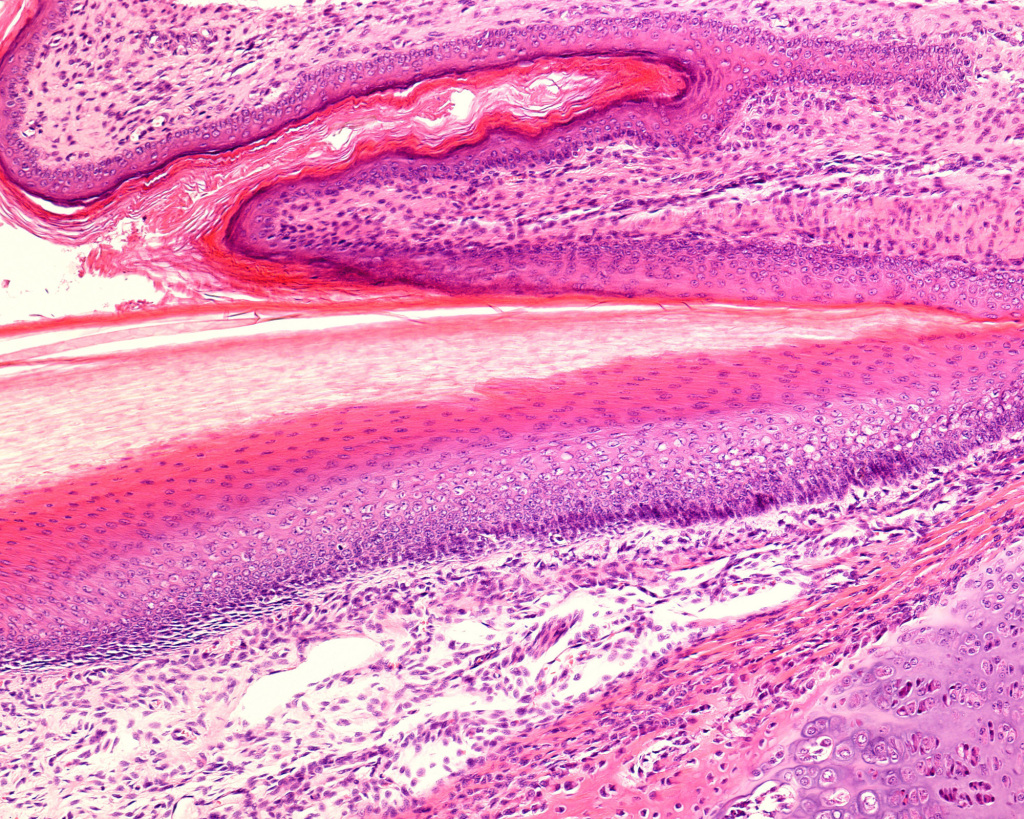

Our medical studies confirmed our interest in histology.